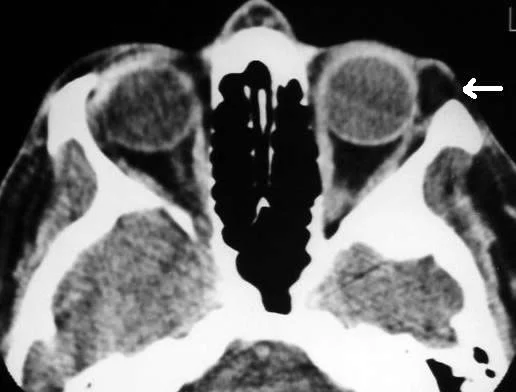

Thyroid Eye Disease

-

Pleomorphic cellular infiltration of EOM>enlargement >degeneration>fibrosis>restrictive myopathy>diplopia.

Infiltration of the orbital fat with chronic inflammatory cells with the accumulation of glycosaminoglycans and water retention>↑orbital content.